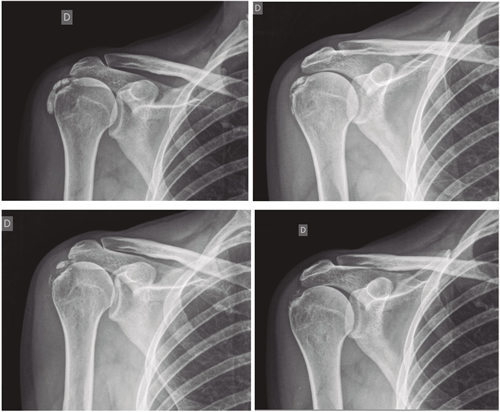

Figura 2